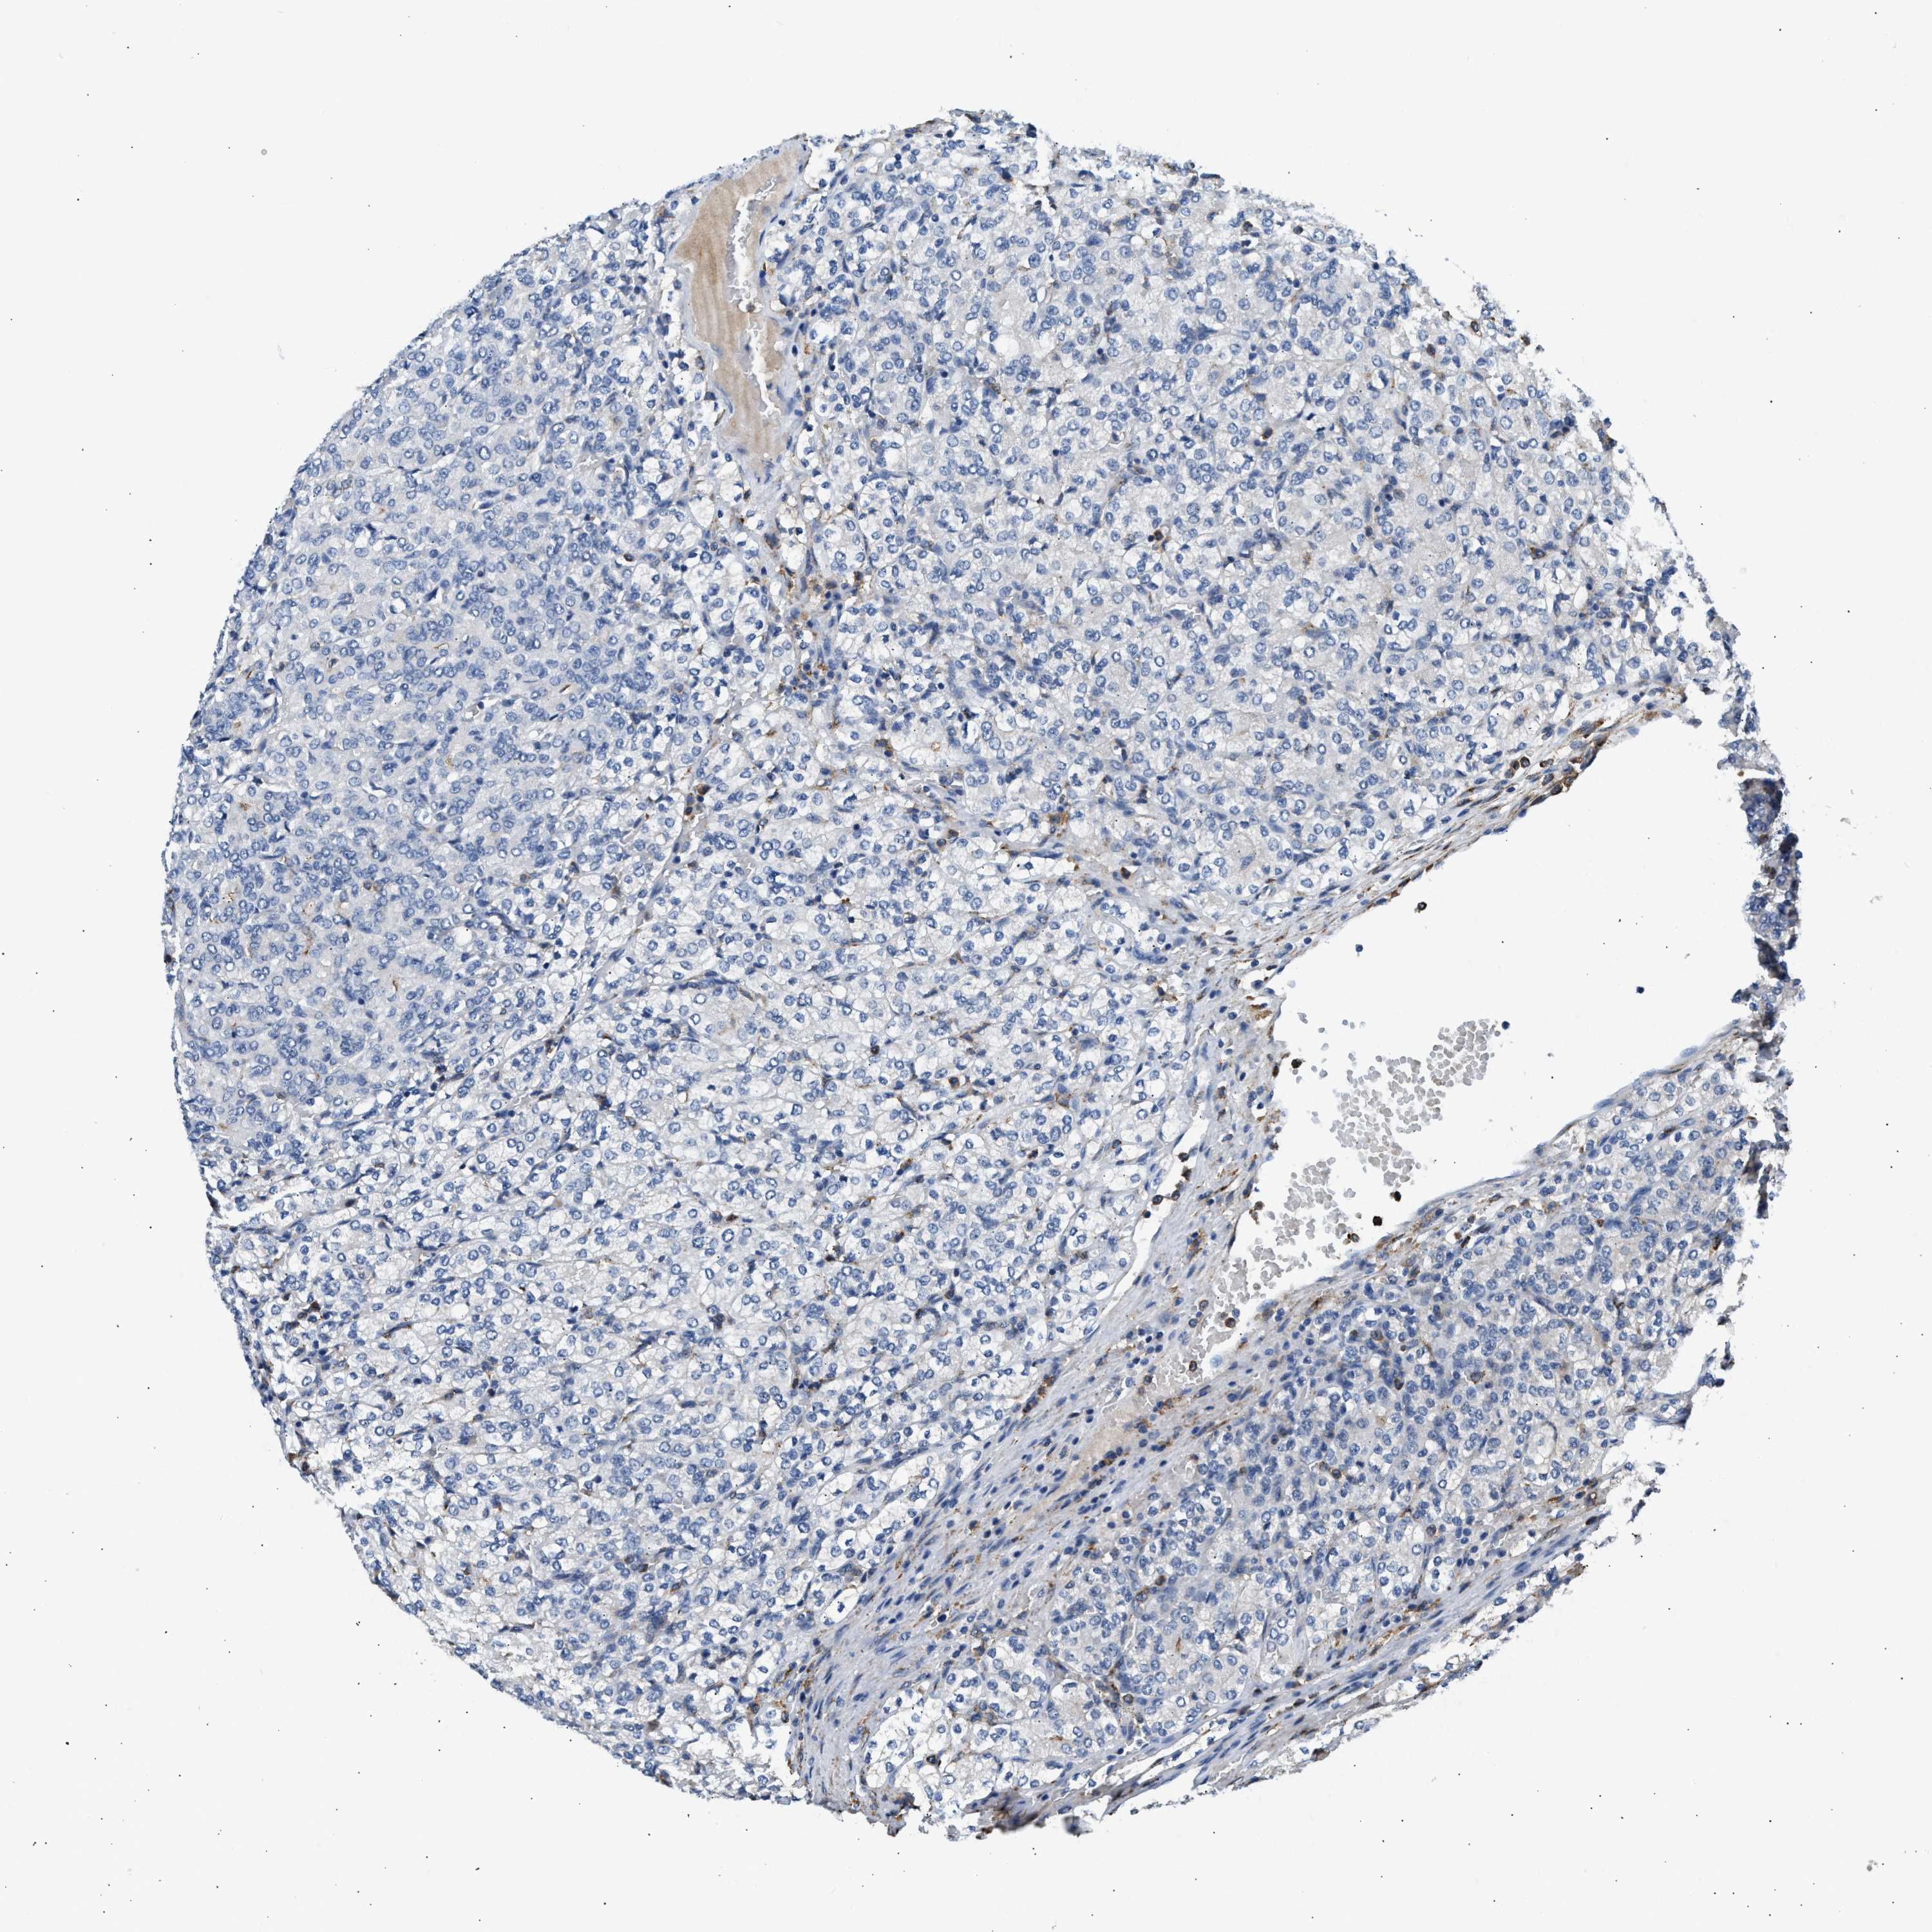

KIDNEY CHROMOPHOBE (TCGA) - Interactive survival scatter ploti

The Survival Scatter plot shows the clinical status (i.e. dead or alive) for all individuals in the patient cohort, based on the same data that underlies the corresponding Kaplan-Meier plots. Patients that are alive at last time for follow-up are shown in blue and patients who have died during the study are shown in red.

The x-axis shows the expression levels (FPKM) of the investigated gene in the tumor tissue at the time of diagnosis. The y-axis shows the follow-up time after diagnosis (years). Both axes are complimented with kernel density curves demonstrating the data density over the axes. The top density plot shows the expression levels (FPKM) distribution among dead (red) and alive patients (blue). The right density plot shows the data density of the survived years of dead patients with high and low expression levels respectively, stratified using the cutoff indicated by the vertical dashed line through the Survival Scatter plot. This cutoff is automatically defined based on the FPKM cutoff that minimizes the p-score. The cutoff can be changed by dragging the vertical line or by entering a cutoff value in the square labeled "Current cut-off".

Under the Survival Scatter plot the p-score landscape (black curve; left axis) is shown together with dead median separation (red curve; right axis). Dead median separation is the difference in median mRNA expression between patients who have died with high and low expression, respectively. It is calculated as follows: median FPKM expression of dead patients with high expression - median FPKM expression of dead patients with low expression. This is intended to aid the user in visually exploring custom cutoffs and the associated p-scores and dead median separation.

Individual patient data is displayed and can be filtered by clicking on one or more of the category buttons on the top of the page. Categories describing expression level and patient information include: high, low, alive, dead, female, male and tumor stages. The scale of the x-axis can be toggled between linear and log-scale by clicking on the "x log" button. Mouse-over function shows TCGA ID, patient information and mRNA expression (FPKM) for each patient.

& Survival analysisi

Kaplan-Meier plots summarize results from analysis of correlation between mRNA expression level and patient survival. Patients were divided based on level of expression into one of the two groups "low" (under cut off) or "high" (over cut off). X-axis shows time for survival (years) and y-axis shows the probability of survival, where 1.0 corresponds to 100 percent.

LRP1 is not prognostic in Kidney Chromophobe (TCGA)

Best expression cut offi

Based on the FPKM value of each gene, patients were classified into two groups and association between prognosis (survival) and gene expression (FPKM) was examined. The best expression cut-off refers the FPKM value that yields maximal difference with regard to survival between the two groups at the lowest log-rank P-value. Best expression cut-off was selected based on survival analysis .

When clicking on this number, the vertical dashed line indicating cut-off, the interactive survival plot, and the Kaplan-Meier curve will be adjusted to show results based on the best expression cut-off.

: 11.66

Median expressioni

Median expression refers to the median FPKM value calculated based on the gene expression (FPKM) data from all patients in this dataset. When clicking on this number, the vertical dashed line indicating cut-off, the interactive survival plot, and the Kaplan-Meier curve will be adjusted to show results based on the median expression.

: N/A

Median follow up timei

Median follow up time refers to the median time (years) after diagnosis with this type of cancer, based on clinical data from all patients in this dataset.

P scorei

Log-rank P value for Kaplan-Meier plot showing results from analysis of correlation between mRNA expression level and patient survival.

N/A

5-year survival highi

5-year survival for patients with higher expression than the expression cutoff.

For melanoma and glioma, 3-year survival is shown.

5-year survival lowi

5-year survival for patients with lower expression than the expression cutoff.

TCGA RNA samplesi

RNA-seq data is reported as average FPKM (number Fragments Per Kilobase of exon per Million reads), generated by the The Cancer Genome Atlas (TCGA) .

Normal distribution across the dataset is visualized with box plots, shown as median and 25th and 75th percentiles. Points are displayed as outliers if they are above or below 1.5 times the interquartile range. FPKM values of the individual samples are presented next to the box plot.

Average pTPM 9.6

Number of samples 64